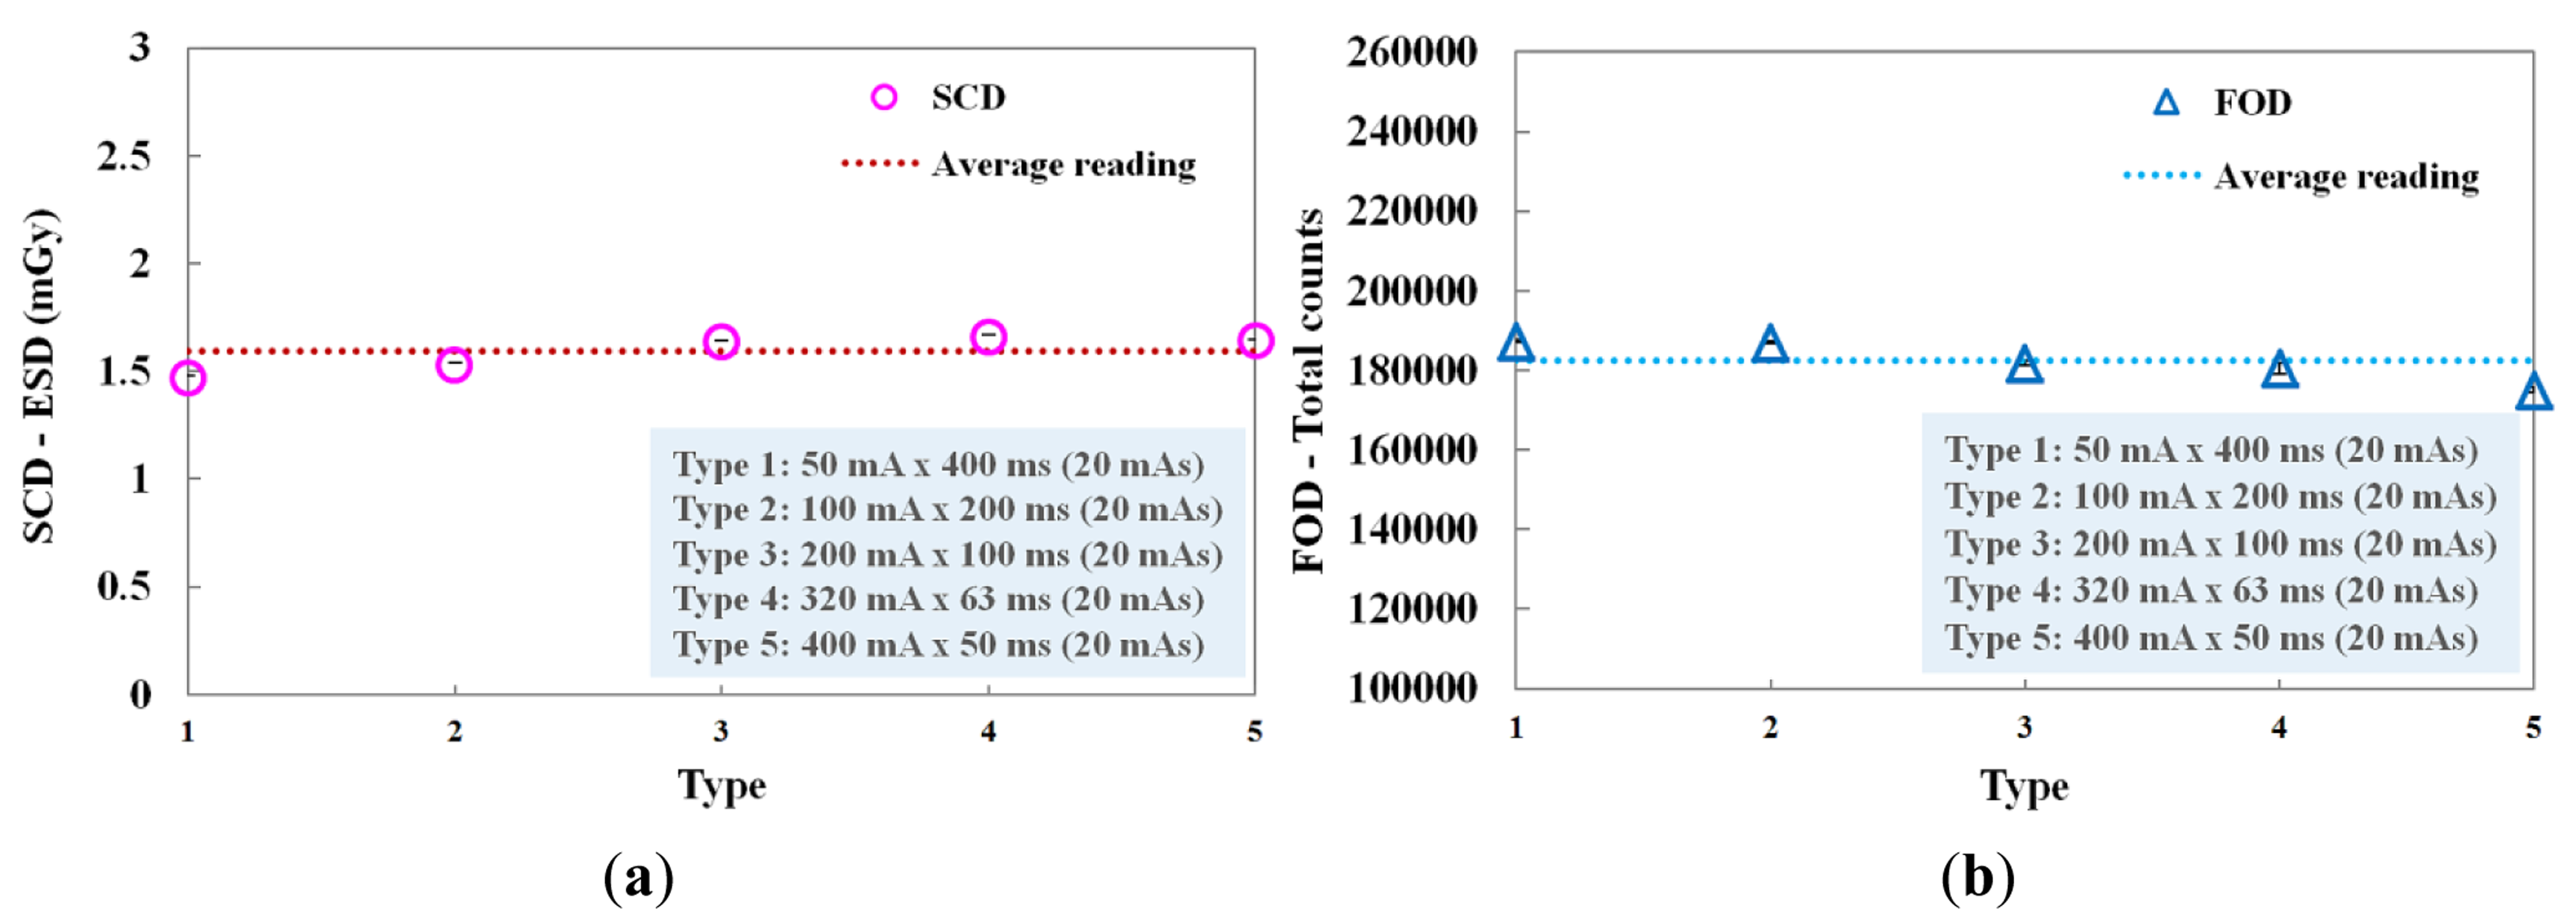

We evaluated the performance of the FOD in accordance with the current-time product, whose values were determined by the product of the tube current (mA) and the irradiation time (ms). Figure 7 shows the ESDs of the SCD and the total counts of the FOD measured at each current-time product. In this experiment, although the tube current and the irradiation time were changed, the current-time product was maintained at 20 mAs. Each combination (i.e., type 1∼5) concerning the product of tube current and irradiation time is presented in Figure 7. At type 5, the total counts value of the FOD was slightly lower than the average reading value and it seems that this phenomenon was affected by the relatively small number of scintillation photons detected when the irradiation time was shorter than 50 ms, as can be seen in Figure 6a. However, when each current-time product was fixed, the total counts of the FOD were almost constant due to the decrease of irradiation time with the increase of tube current, as shown in Figure 7b. Therefore, we demonstrated that the total counts of the FOD are only affected by the ESD values even when each exposure parameter is changed independently.